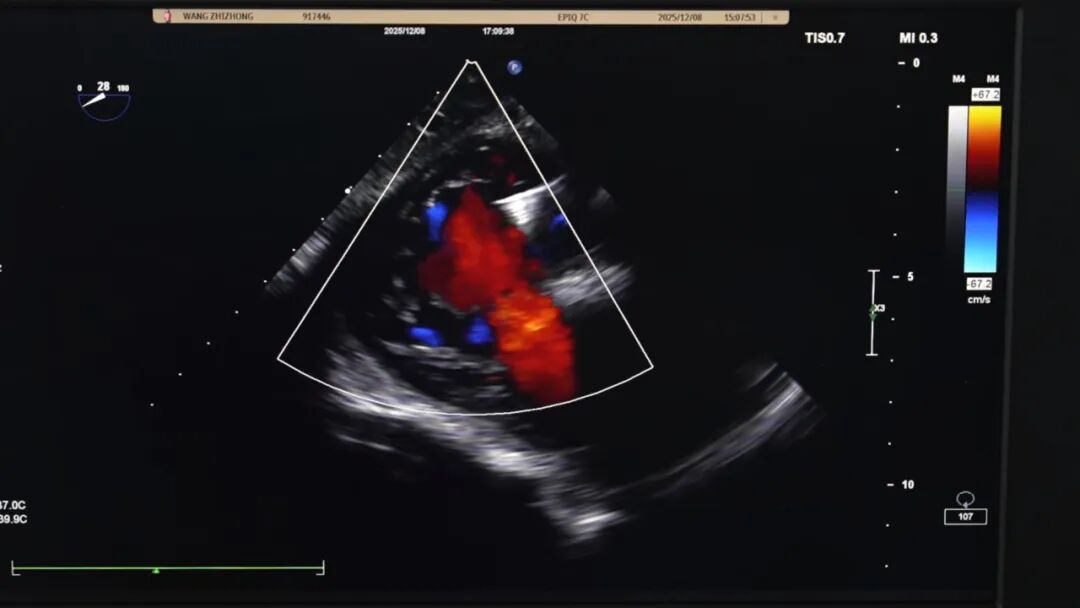

术后监测数据令人振奋:二尖瓣、三尖瓣反流几乎消失,达到理想治疗效果。如今,老先生胸闷、气喘的症状已彻底缓解,能够自主活动,精神状态明显好转,很快就能康复出院。